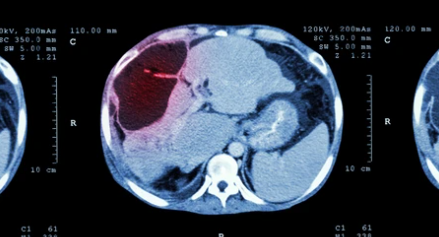

간암은 초기에는 증상이 없어 조기진단이 어렵습니다. 그래서 정기적인 간암 검진을 받아야 합니다. 간암 검진은 혈액검사, 초음파, CT, MRI 등의 검사를 통해 진행됩니다. 간암 검진은 매년 정기적으로 받는 것이 좋습니다.